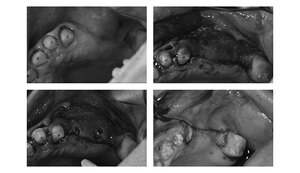

【担当医師所見】

左下奥歯は親知らずが原因でクラウン(かぶせ物)の下まで虫歯になっています。 またその手前の歯は根中央部に大きな透過像(黒い像)が見られます。クラウン除去後、マイクロスコープ下で確認したところ中央部は亀裂が入り保存不可能な状態になっており抜歯となりました。

また右上6番にも大きな透過像があり虫歯となっていることがわかります。

①親知らず手前の歯はクラウン(白い不透過像)直下に大きな透過像(黒い部分)が見られこのような場合は抜歯になる確率が高いです。

②歯根分岐部(中央部)に及ぶ歯周炎ー根尖性歯周炎の原因はクラウン除去後にマイクロスコープ下にて破折線を確認したため抜歯となりました。

右下の大臼歯部は抜歯後治癒を待ち、骨造成とインプラント埋入を同時に行いました。上部構造はFCZ(ジルコニアセラミッククラウン)となっています。

また左下の親知らずは虫歯のため抜歯、左下7番と5番はセラミックインレー、6番はFCZにて補綴しました。